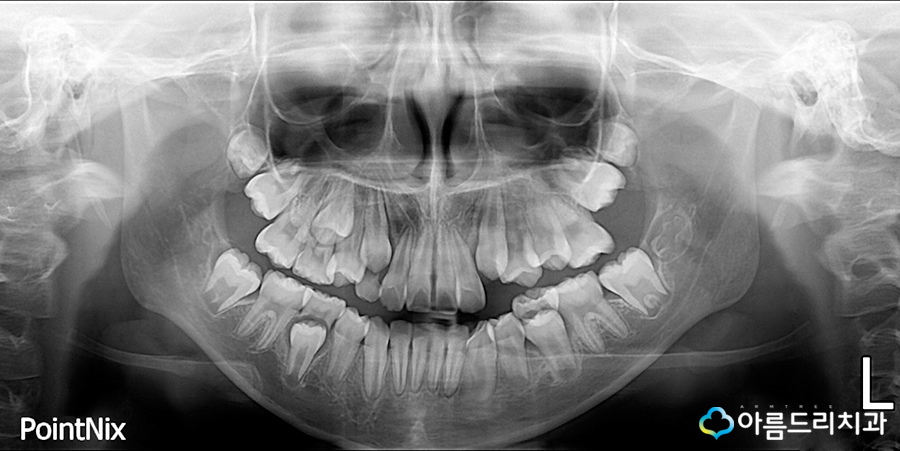

파노라마 엑스레이를 통하여 전체 치아의 배열과 상태, 교합관계나 턱뼈의 상태 등 턱 얼 굴 구조의 위치관계를 한눈에 알수 있습니다.

어린이치아교정을 할 때 성장 및 치아와 골격 진단을 보다 정밀하게 하기 위해 두부방사선 사진을 촬영하게 되는데요~ 이는 위턱과 아래 턱의 교합관계와 치아관계 등의 골격적인 문제 를 확인하는 용도로 쓰이고 있으며 이를 통해 골격 문제에 대한 분석과 계획을 세우게되죠.

위의 두가지는 성인교정과 어린이부정교합의 경우 마찬가지로 채득하게 되는 자료입니다.